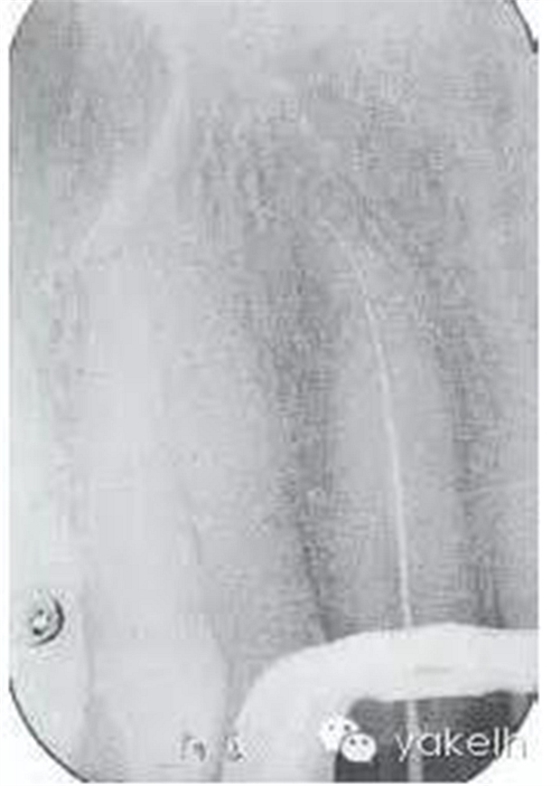

¤¤局麻下,制備上頜切牙印模;拆除12烤瓷全冠;評估患牙的可修復性;橡皮障隔離患牙,定位根管口,使用GG鉆和不銹鋼手用銼去除根管內(nèi)的牙膠;全程使用大量次氯酸鈉沖洗根管;根尖定位儀測量根管工作長度,拍攝X線片確定(圖6.3.3);使用不銹鋼手用銼和鎳鈦旋轉(zhuǎn)器械進行根管預備,EDTA沖洗根管,再用次氯酸鈉進行終末沖洗;紙尖干燥根管;使用牙膠輔以根管封閉劑、采用熱垂直加壓技術充填根管的根尖5mm;建議樁核冠修復。

圖6.3.3 確定工作長度的X線片顯示,12根管通暢至全長;特征是根管的根尖1/3向遠中腭側(cè)彎曲。